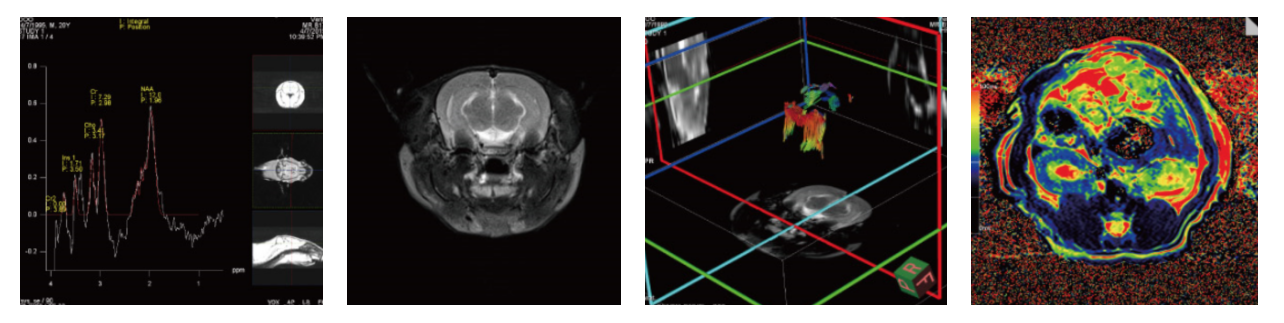

西门子Vida小动物核磁共振成像,拥有16通道老鼠线圈,另可配套新西兰大白兔线圈。线圈能够实现弥散、灌注、DTI、 MRS. BOLD等多种功能成像,可用与以下4个方向研究。

图1 小动物核磁共振成像仪(西门子、vida)

图2 结果展示